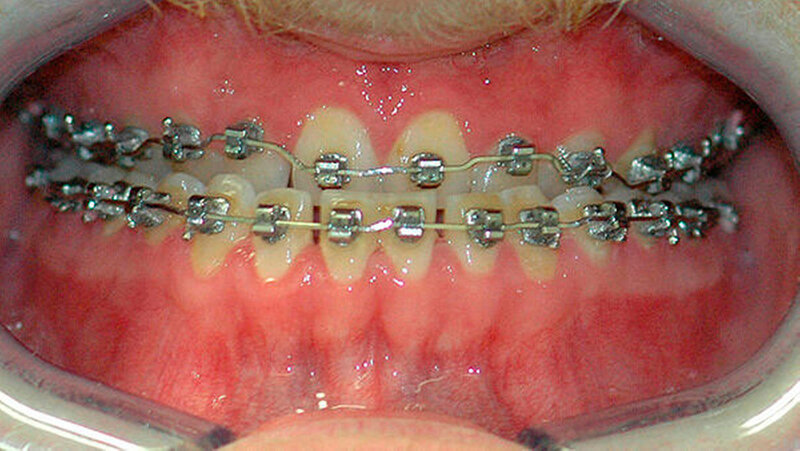

Im Oktober letzten Jahres stellte sich Thomas M. (Name von der Redaktion geändert) erstmals in der Stuttgarter Spezialsprechstunde für Kieferfehlstellungen vor. Die Ausformung der Zahnbögen durch den behandelnden Fachzahnarzt für Kieferorthopädie ist bereits fortgeschritten. Eine operative Umstellung der Kieferknochen kann somit relativ zeitnah erfolgen.

Die Abbildungen 1 und 2 zeigen die klinische Situation bei Erstvorstellung: Der Unterkiefer ist zu prominent. Der Oberkiefer und das Mittelgesicht liegen zurück. In der Front liegt ein umgekehrter Überbiss vor. Der Unterkiefer steht vor dem Oberkiefer. Das erschwert das Abbeißen und Kauen der Nahrung. Die Scans (siehe Abbildungen) dokumentieren, wie aufwendig die virtuelle Operationsplanung erfolgen musste.